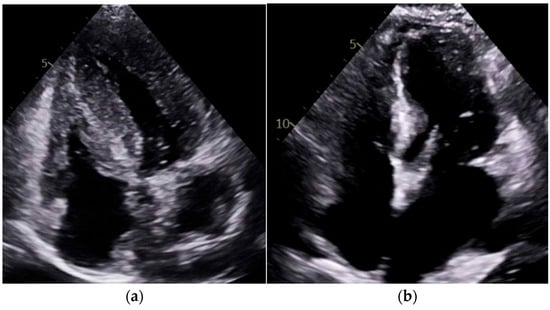

Our study found significantly greater IVSd and LVPWd in amyloidosis compared to sarcoidosis, consistent with prior reports on echocardiographic findings in amyloidosis namely, pronounced LV wall thickening and diastolic dysfunction (Figure 1 and Figure 2). Ref [24], Conversely, TTE offers limited sensitivity in sarcoidosis, functioning mainly to prompt further diagnostic imaging when regional wall thinning or basal septal changes are detected [25]. Our CMR findings revealed focal or patchy LGE in sarcoidosis, as well as mismatch uptake patterns on PET, which parallels the existing literature that utilizes CMR for structural analysis and FDG PET for monitoring active inflammation [26,27]. Our findings in the CA cohort corroborate that PYP scintigraphy (with a negative monoclonal protein screen) remains highly specific for transthyretin cardiac amyloidosis [28]. Additionally, all 19 of our CA patients undergoing CMR exhibited a diffuse pattern of LGE, highlighting the global amyloid infiltration of myocardium in contrast to the patchy granulomatous infiltration in CS. More specific measures on CMR such as Native T1 mapping and ECV measurements can indicate the extent of amyloid infiltration [29]. Unfortunately, only 19 of the 125 amyloidosis patients underwent CMR in our study, which limited the robustness of sub-analyses in this domain (Figure 3 and Figure 4).

Figure 3.

Cardiac MRI examples of late gadolinium enhancement (LGE). (a) Four-chamber view showing septal LGE (scar). (b) Short-axis view demonstrating a large inferolateral scar. Both (a,b) demonstrate the patchy LGE pattern characteristic of cardiac sarcoidosis, marked by the yellow arrow. (c) Four-chamber view and (d) short-axis view showing diffuse subendocardial and transmural LGE in a global distribution, consistent with cardiac amyloidosis.